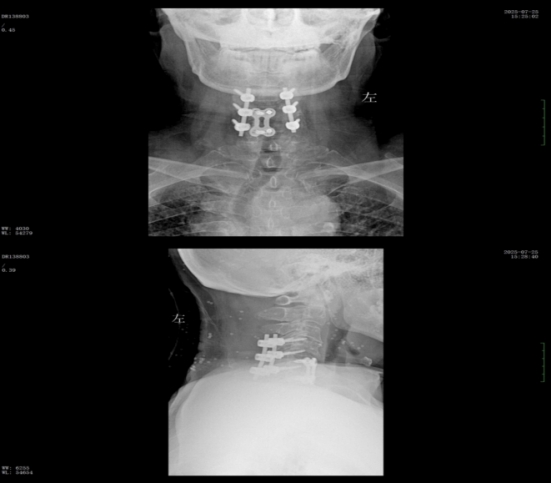

經(jīng)過(guò)精準(zhǔn)手術(shù)和術(shù)后系統(tǒng)的康復(fù)治療,患者神經(jīng)功能得到明顯恢復(fù),四肢肌力及感覺(jué)逐步改善,術(shù)后肌力達(dá)到IV級(jí)左右。復(fù)查X線顯示內(nèi)固定位置理想,患者非常滿意。出院之際,患者及家屬對(duì)衡陽(yáng)市中心醫(yī)院的醫(yī)療技術(shù)、護(hù)理服務(wù)及醫(yī)聯(lián)體轉(zhuǎn)診效率均給予高度評(píng)價(jià)。

wps2.jpg

術(shù)后x線內(nèi)固定位置理想